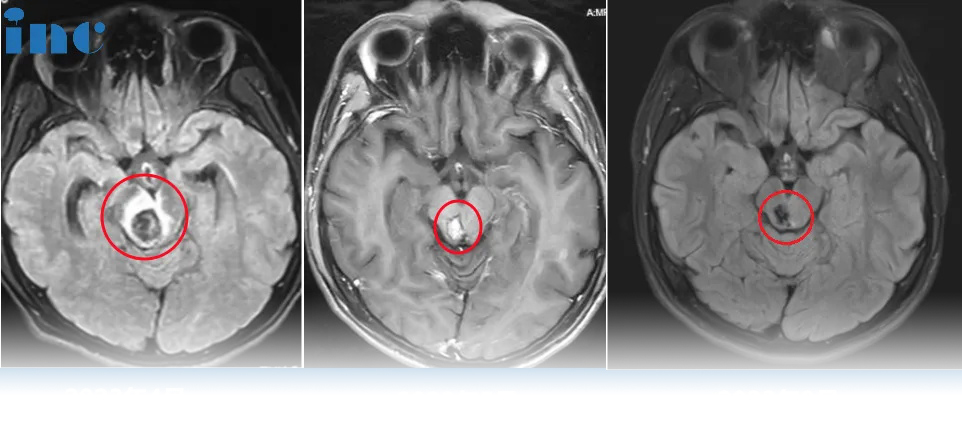

海绵状畸形(CMs)是中枢神经系统的血管造影性隐匿,低流量血管畸形。它们占全部血管畸形的8-20%。6-7岁患者的出血率可达6%...

虽然脑干海绵状血管畸形一度被认为不能手术治疗,但在病人选择、手术暴露、术中MRI引导、MR纤维束成像和神经生理学监测等方面的改进已使大多数手术...

海绵状血管瘤能根治吗?海绵状血管瘤是一种颅内的血管畸形,经过手术切除是可以治好的,但重要位置的病变考验术者的经验和技巧...

很用力咳嗽了几下,还咳出了脑干出血?真有这样的事吗? 41岁的宋女士于2023年10月底,因感冒喉咙有痰,很用力咳嗽了几下,随后出现视物模糊,重影,...